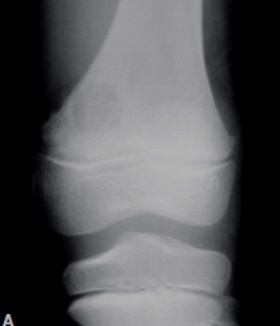

2

Q

Qual diagnóstico?

A

Lesão na apófise

Fise aberta

Dx: Condroblastoma